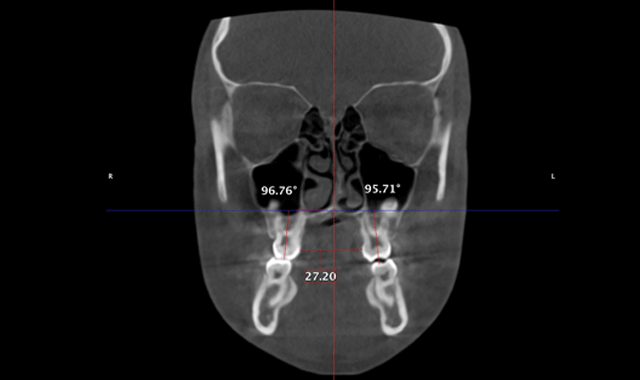

We can now extrapolate a coronal view that allows us to visualize many anatomical structures to formulate a diagnoses and treatment plan. The coronal view with a slice taken through the lingual roots of the maxillary first molars can be used to accurately determine the width of the maxilla and the inclinations of the maxillary molars (Fig. 5). We can then determine the mechanics needed for our patients in this dimension. The mechanics utilized on the patient in Figure 5 were expanded with skeletal fixation of the expander. No bands were attached to the molars.

Therefore, true horizontal expansion was achieved (Figs. 6a, 6b, 6c). These images were taken at the ULD settings on a Planmeca ProMax 3D Mid. Before placing stainless steel wires, many orthodontists will take a progress pan. to evaluate the roots of the teeth as far as proper bracket placements. This is an additional 35 microsieverts when using a traditional 2D panoramic machine. The ULD setting on the Planmeca Pro-Max 3D Mid machine with a limited field of view that only images the teeth is an effective dose of around 9 microsieverts.